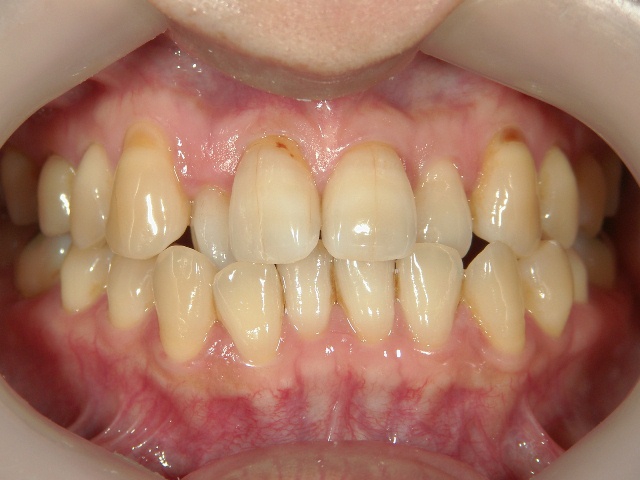

矯正歯科 治療前 正面

矯正歯科 治療後 正面